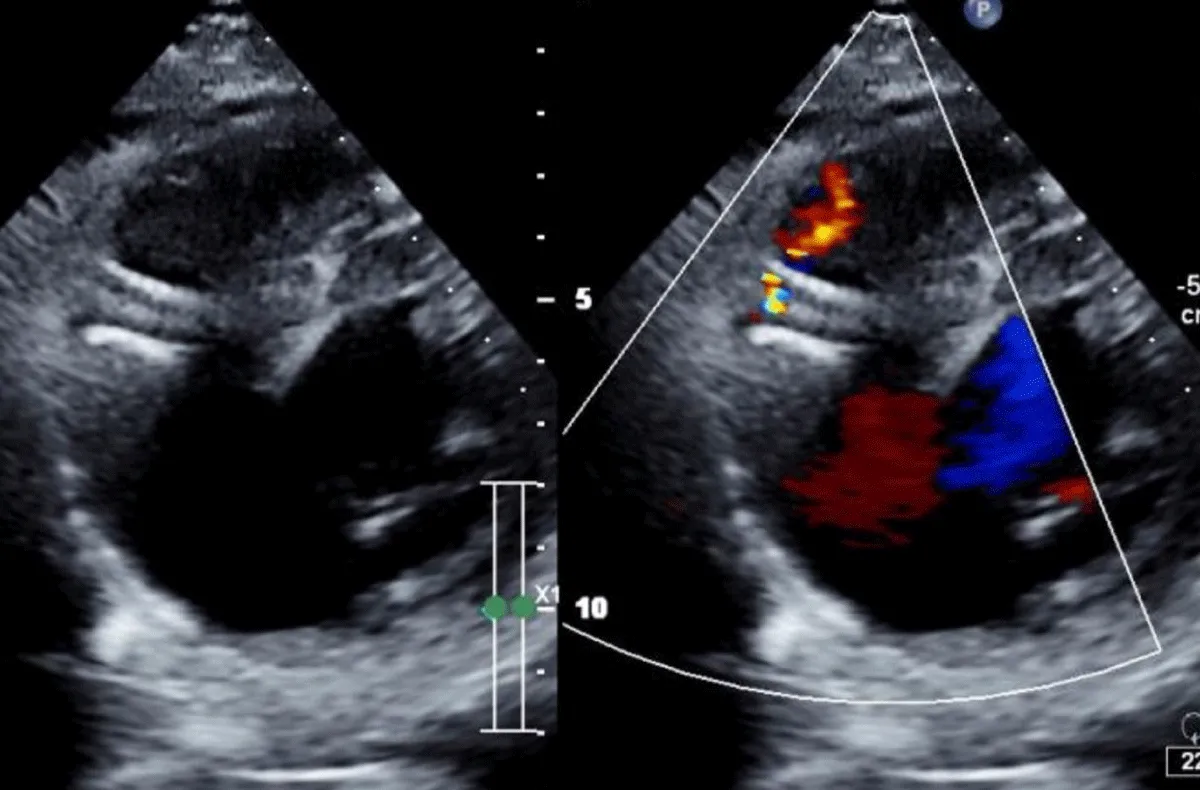

The technique of percutaneous closure of a VSR is based upon the well-proven and widely accepted percutaneous congenital ventricular septal defect closure. Transthoracic echocardiography (TTE) with colour Doppler was used to determine the size and anatomy of the VSR in all cases (Figure 1).

Figure 1: Transthoracic echocardiography (TTE) with colour Doppler to determine the size and anatomy of the VSR.